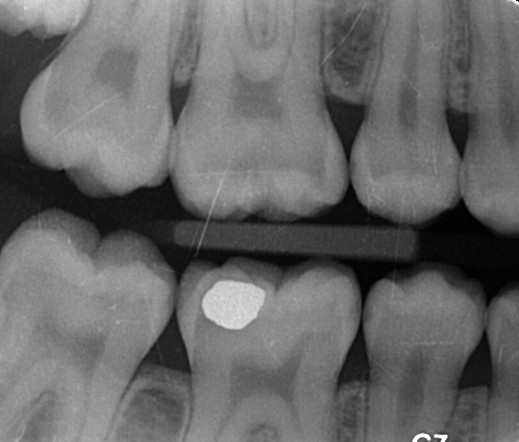

Farvestoffer til afsløring af plak på tænderne. Selv efter tre uger uden tandbørstning er der plakfri områder. Et område uden plak er et cariesfrit område. Med regelmæssig brug af tandbørste og tandtråd er det muligt helt at fjerne cariestruslen. Kun steder hvor plakken ikke fjernes regelmæssigt kan der opstå caries. I naturen er det den grove kost der fjerner plakken. Glatte tandoverflader er en evolutionær genistreg, der letter plakfjernelsen på de flader der udsættes for mindre slid. Formålet med regelmæssig plakfjernelse er at få fjernet plakken fra de tandoverflader, hvor almindelig tygning ikke fjerner plakken (plak-stagnations-områderne). (Else Theilade).